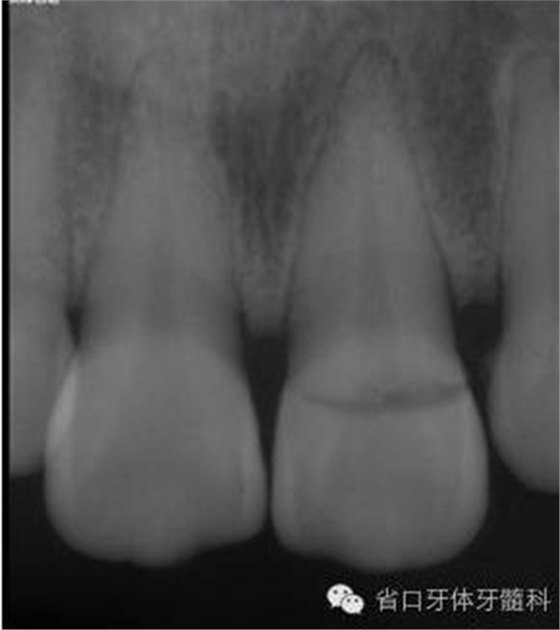

圖3. 術前X線片

圖8. 21/行根管治療術,保留根尖約5mm的根充物,根中上段預留空間以預備纖維樁道。